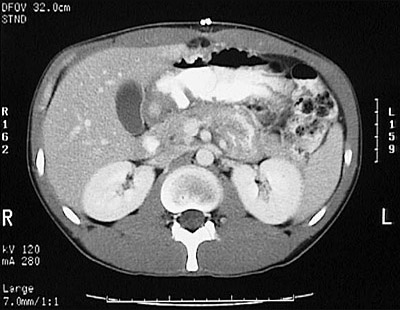

[L2] This is a normal abdominal CT scan with contrast demonstrating the liver and spleen and gallbladder and gastric antrum and pancreas and colon and right kidney and left kidney and aorta and psoas muscle in the abdomen.